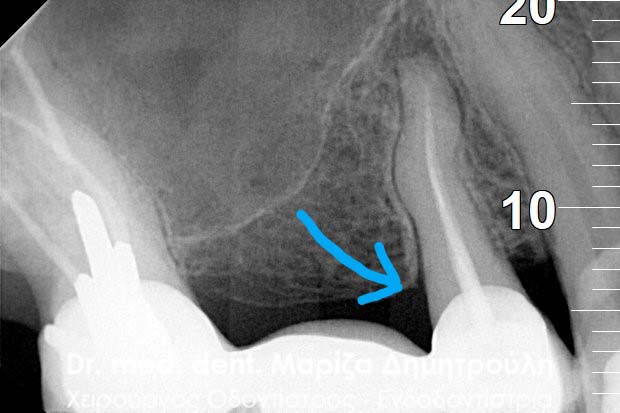

Μετά από τη χορήγηση τοπικής αναισθησίας και την τοποθέτηση ελαστικού απομονωτήρα ακολούθησε η διάνοιξη του δοντιού. Αμέσως μετά την αφαίρεση του προσωρινού σφραγίσματος παρατηρήθηκε έντονη και απότομη αιμορραγία του δοντιού, η οποία προερχόταν από ένα συγκεκριμένο σημείο. Η κλινική αυτή εικόνα επιβεβαίωσε τις υποψίες για διάτρηση του δοντιού. Εντοπίστηκε το σημείο της διάτρησης και έγινε έλεγχος με μία ακτινογραφία. Στη συνέχεια πραγματοποιήθηκε η αποκατάσταση της διάτρησης με ειδικό υλικό και εντοπίστηκε ο τρίτος σωλήνας του δοντιού. Η όλη διαδικασία επιβεβαιώθηκε με τη λήψη ακτινογραφίας.

Εντοπισμός του τρίτου ριζικού σωλήνα